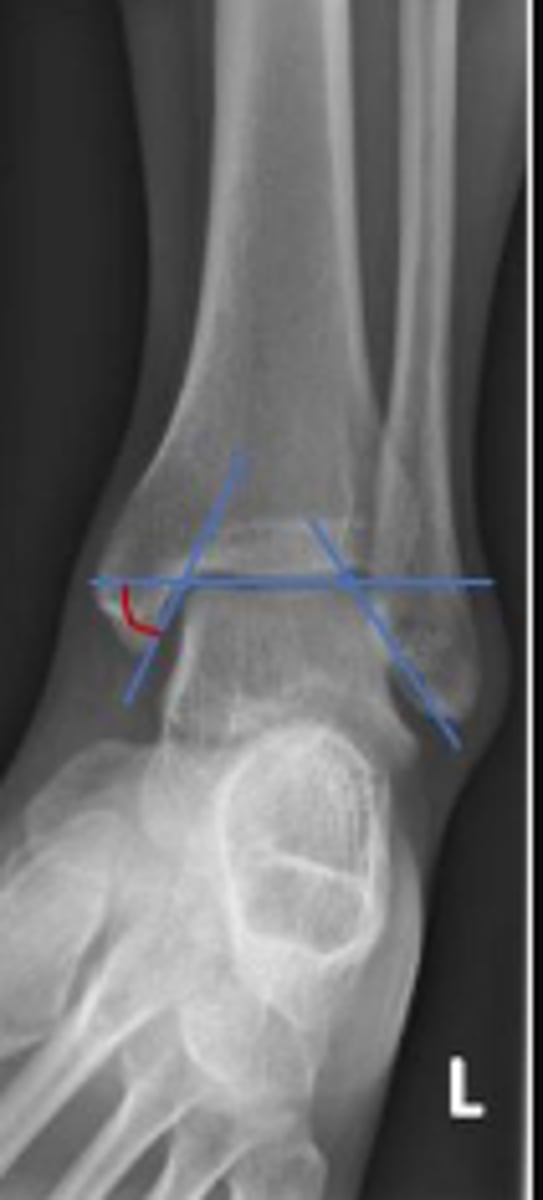

Axial relationship of the ankle

What is the overarching name of the assessment?

Tibial angle & fibular angle

What are the 2 components of the assessment?

Tibial angle

What is the name of the assessment?

Yes

Is the assessment within normal limits?

Fibular angle